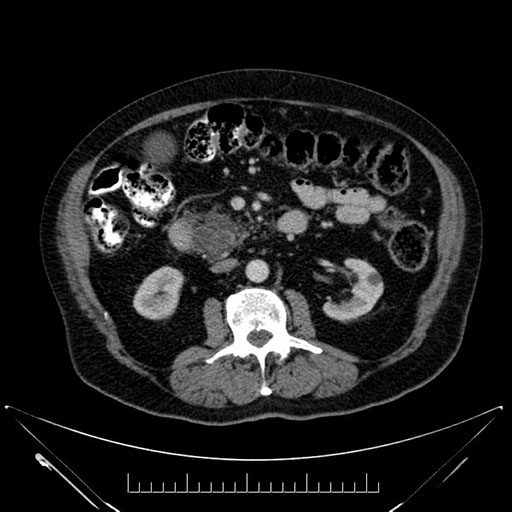

Imaging Analysis

Look through the patient's CT scan to identify any areas of concern for the necessary procedure.

Based on your CT findings, which issue(s) would give reason for "planned slowing down moment(s)" in this case?